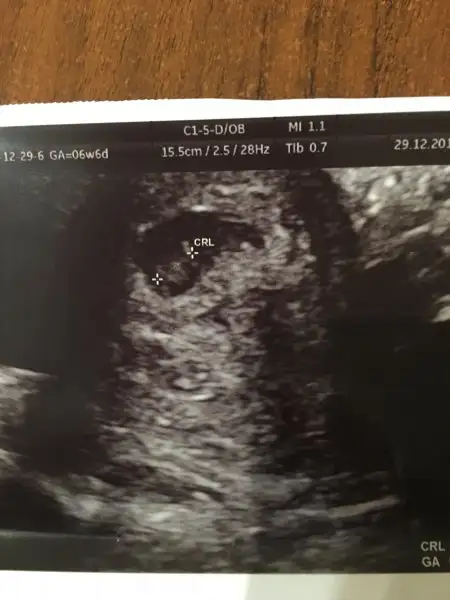

Canım merhaba banada yardımcı okuraan sevinirim karından bakıldı sata göre 6+4 sence kızmı erkekmıErkek gibi canim

canım karından bakıldıysa solda ve erkek.Kimse yokmu hanımlar cevap verecek üstte benim resimler. Tecrübeli hanımlar merak ediyorum lürfen

Karından ıltrason inaşşaah karfeşim öyledir 3 tane prensesten sonra sağlıklı bir erkek olur. Ben ve eşim sıkıntı hiç bir zaman yapmadık ama toplum devamlı imalı laf sokmalarından sıkıldım .canım karından bakıldıysa solda ve erkek.

vajınal ultrasonsa kız

buna gore erkek canım. benım karından boyleydı doktor kıza benzıyor dedı. kesındegıl benımkıde ama kesnlesırse teorı bnde tuttuEki Görüntüle 1939188 Eki Görüntüle 1939187 Kizlar banada baksanizaa altan utrasyon yani vajenden

Kızlarr nerdesiniz cevap yok muEki Görüntüle 1939127 Eki Görüntüle 1939128 Kızlar bana da bakar mısınız karından ultrason ve üstteki 9 hafta alttaki 7 haftalık

6+3 falan karindan :) plesanta nerede ya kiz mi erkek miyardimmmmm